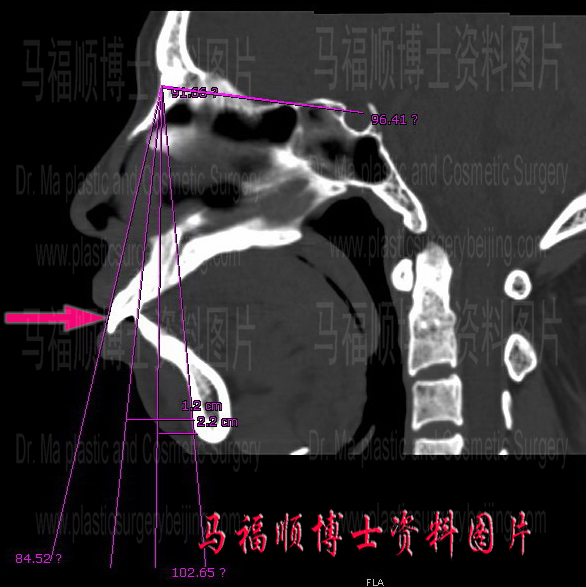

上下颌前端截骨后推术,是指将上颌骨与下颌骨的前端截开,并去除一小部分骨头,然后将切下来的部分后推,以达到改善突嘴外观的目的。与 Lefort I 型截骨不同,由于这一手术只在上下颌骨的前端截骨,所以要拔牙以腾出空间来实现上下颌骨的后移。有些受术者担心拔牙后会不会留下很大的牙缝。回答是不会的,因为有牙齿在会妨碍颌骨的后推才拔牙,拔牙后的空隙在颌骨后推时,依据后移量的不同,会完全或接近完全闭合,所以术后不会就掉牙的感觉,最多会是出现有关牙缝稍大的情况。